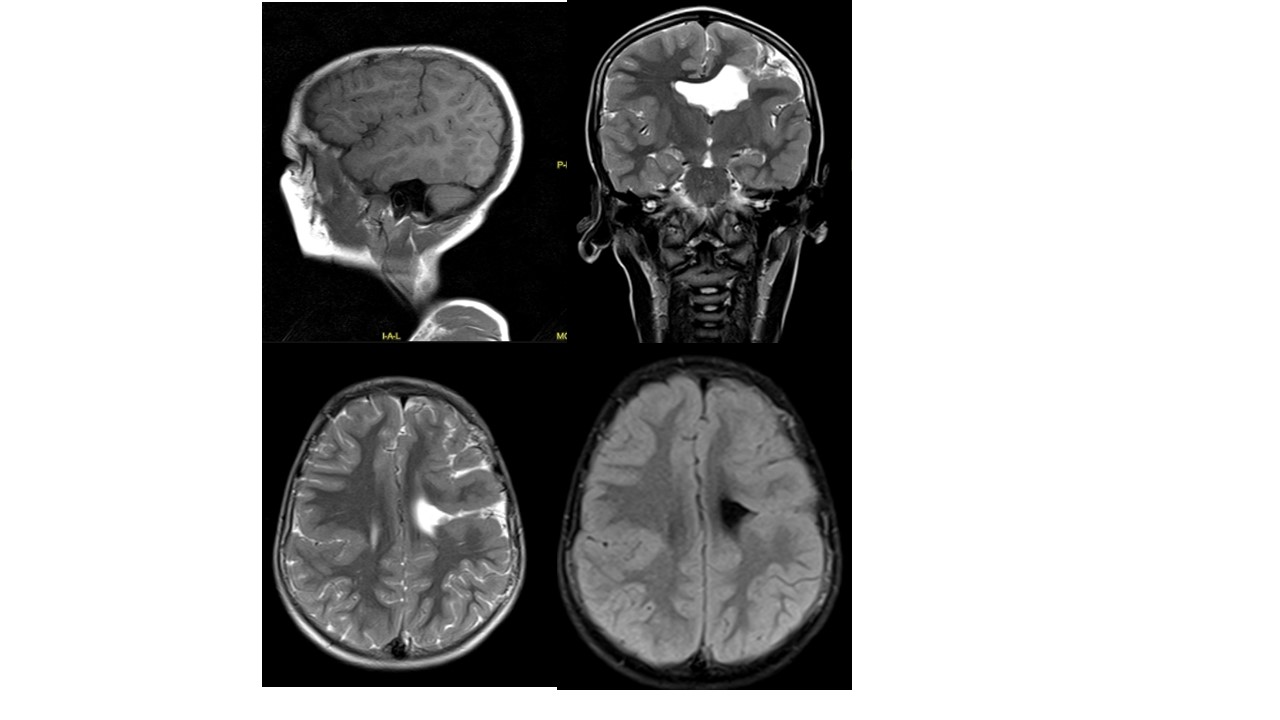

Question: Name the anomaly seen in the MRI here:

Correct Answer: Schizencephaly

Explaination: Right side Closed lip schizencephaly (Type- I) not communicating with the ventricular system<br><br>Left side open lip schizencephaly (Type- II) communicating with the ventricular system<br><br>The defect is characterized by the presence of a cleft in the brain extending from the surface of the pia mater to the cerebral ventricles. The margins of the cleft are lined with heterotrophic, dysplastic gray matter. The most common location of the anomaly is the frontal lobe and the region of the lateral sulcus

Reference: Neto, H. Bilateral schizencephaly (open and closed lip). Case study, Radiopaedia.org.https://doi.org/10.53347/rID-52574